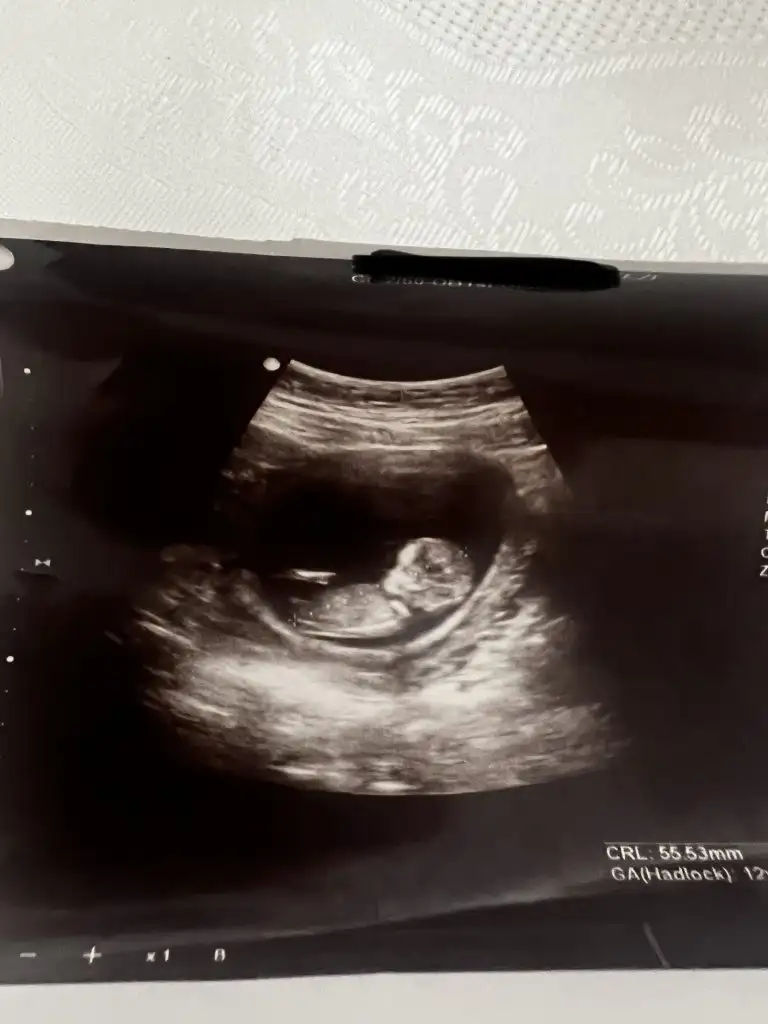

Kızlar selam. Yumurtlama sürecimi hiç takip etmediğim için maalesef bilmiyorum, bu konuda tecrübelerinize ve desteğinize ihtiyacım var. SAT 25 Şubat, 10 Mart'ta lekelenme ve ağrı başladı. Lekelenme ve ağrılar tam 16 gün sürdü, 25 Mart'ta bitti. Dayanılmayacak gibi değil fakat zaman zaman artan (ağrı kesiciye ihtiyaç duyulan), zaman zaman ise hafifleyen/kaybolan bel ve kasık ağrıları bu süre içinde hep devam etti. Reglden 14 gün sonra başladığı için yumurtlama olduğunu düşünüyorum. Ancak süre çok uzun geldi. Doktora gittim fakat net bir yorum yapamadı. Dış gebelik veya yumurtlama olduğunu düşünerek beta-hcg istedi. Pozitif çıkarsa tekrar gelirsin, negatif çıkarsa yumurtlamadır dedi. Sonuç negatif (2) çıktı, araya bayram da girince tekrar gidemedim. Henüz regl olmadım, reglimi hangi günden hesaplayacağımı da bilemiyorum. Sizce yumurtlayamama ya da yumurtamın çatlayamaması gibi bir durum olabilir mi? Veya dış gebelik, kimyasal gebelik tarzı bir şey? Benzer bir durum yaşayanınız oldu mu?

Ultrason görüntüsü de 17 Mart tarihine ait. Yani döngümün 21. günü. Belki USG ultrason görüntüsünden anlayan birileri çıkar :(